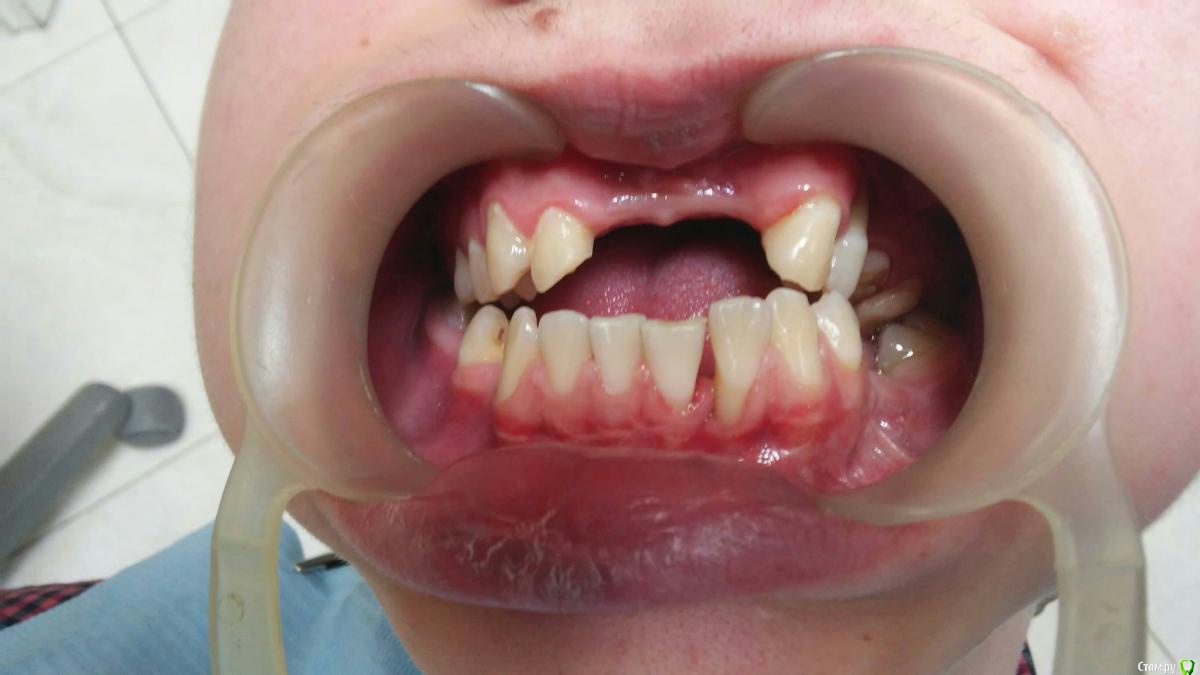

ANCHOUSE Опубликовано 21 апреля, 2015 Поделиться Опубликовано 21 апреля, 2015 (изменено) Пациент,19 лет,реабилитация после дтпНаправлен из стационара на ортодонтиюРецессии 31,32(подвижен 1ст.),2424,32 на удаление 100%? Изменено 21 апреля, 2015 пользователем ANCHOUSE Ссылка на комментарий

ANCHOUSE Опубликовано 21 апреля, 2015 Автор Поделиться Опубликовано 21 апреля, 2015 Парня сбил грузовик,последствия тяжелые,рецессии это уже лирика...... Насчет 32 сомнений нет,там потеря кости значительная,подвижность большая,а вот 24-пат.подв. нет,м\з перегородки сохранены.Еще очень плохая гигена,что усугубляет картину...Должет подойти на к/осм. после проф.гигиены со снимком... Ссылка на комментарий